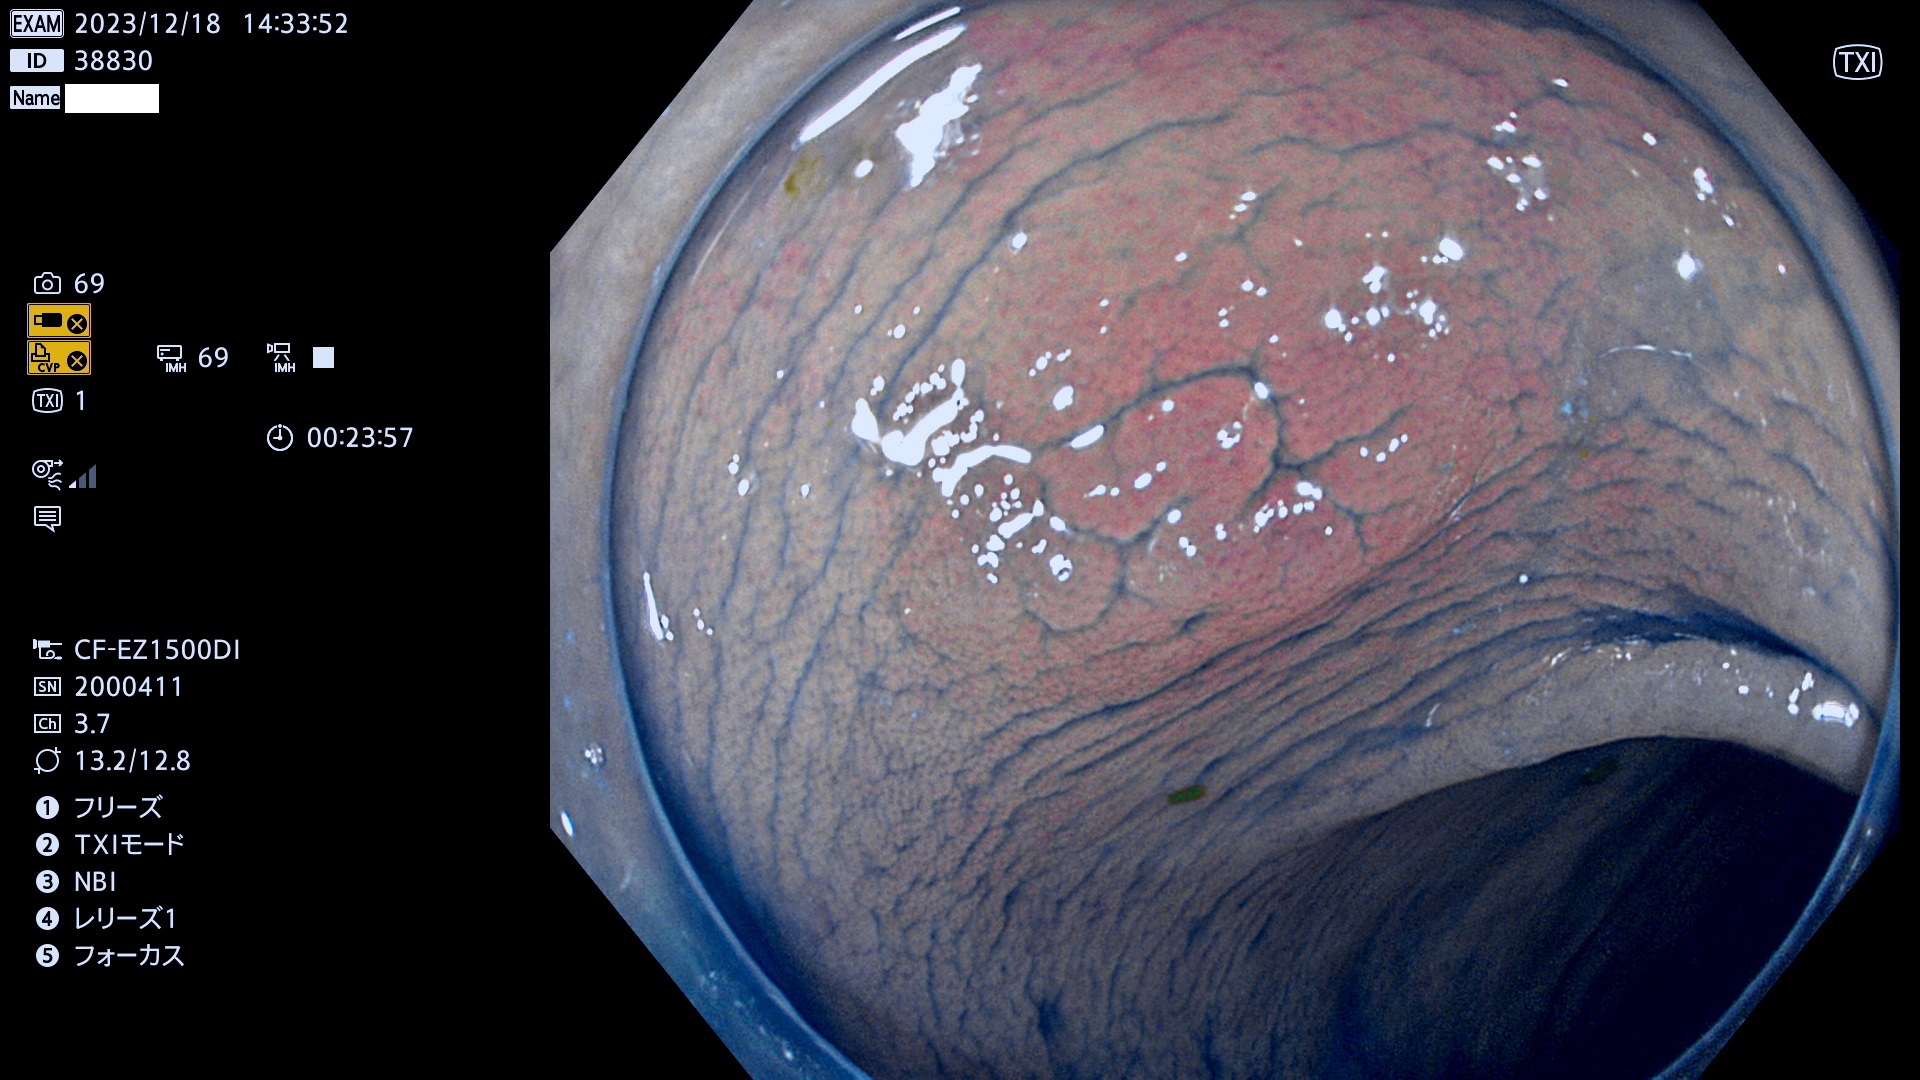

ビランと紛らわしいUc型腺腫(最も危険な前癌病変)

以下は当院で経験した「ビランと鑑別の難しいUc型腺腫」です(全て、病理で腺腫を確認済み)。

このような病変は表面を拡大観察しても診断は不可能であり、現在の内視鏡診断の「限界を超えた病変」と言えます。現実的な対策は「典型的なビランと異なる」と感じたら、「コールド法で積極的に切除する」ことと考えます。もちろん「結局はビランだった(不要な過剰切除だった)」ということもあります。しかしコールド法なら重篤な合併症は稀であり、医師は切除を躊躇すべきではないと考えます。